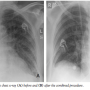

Case Report. An 84-year-old, diabetic, hypertensive and obese woman presented with a non-ST segment elevation myocardial infarction and impending pulmonary edema. She gave history of recently worsening dyspnea on minimal exertion (New York Heart Association class III) together with effort angina on mild exertion with marked limitation of her ordinary activity (Canadian Cardiovascular Society class III) over the previous 6 months. Cardiac examination revealed the presence of a harsh ejection systolic murmur over the cardiac base radiating to the neck (grade IV), and bilateral fine rales were audible over the basal and mid fields of her lungs, denoting pulmonary congestion. Her electrocardiogram showed ST-segment depression and T-wave inversion in the lateral chest leads (V3–V6) together with leads I, aVL and lead II (Figure 1), and her chest x-ray confirmed the presence of severe pulmonary congestion (Figure 2A). Troponin T, total creatine kinase (CK) and CK-MB were elevated. An echocardiography done a few months before admission showed evidence of severe aortic stenosis, yet the patient

The patient was kept in the intensive care unit for 3 more days and then transferred to the department for further management and rehabilitation. She reported rapid relief of her symptoms with marked improvement in her functional capacity (Figure 2B). Dual antiplatelet therapy (aspirin 100 mg/day and clopidogrel 75 mg/day) was advised for 6 months, and aspirin was prescribed lifelong. Thirty-day follow-up echocardiography revealed a well functioning